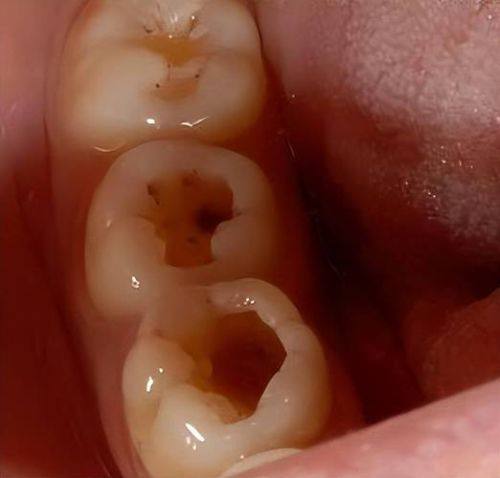

当发现有龋齿时,专精治疗是关键。口腔医生会先清除腐败的牙体组织,就像打扫房间一样,把坏掉的部分清理干净。然后,会用复合树脂或玻璃离子水门汀等材料来填充龋洞,让牙齿修复原本的形态和功能。如果是中深度龋坏,可能还需要垫底来保护牙髓,重度的情况甚至需要进行根管治疗。早期进行专精治疗,可以避免龋齿的腐蚀扩散到牙本质深层,减少后续的治疗痛苦和费用。所以,一旦发现牙齿有问题,要及时去看医生,让专精的治疗为你的牙齿健康保驾护航。

窝沟封闭,阻断致龋菌环境

磨牙的深窝沟是容易藏污纳垢的地方,也是龋齿的高发区域。窝沟封闭就是在这些深窝沟上覆盖一层封闭剂,阻断致龋菌代谢产酸的环境。这种方法适用于儿童新萌出的恒牙,以及成人还未龋坏的深窝沟。封闭剂可以持续保护牙面2 - 5年,大大降低了龋齿的发生几率。就像给牙齿的深窝沟加上了一道防护门,让致龋菌难以入侵。